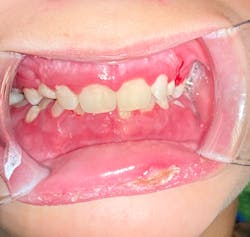

This 12-year-old presented with his mom for a dental visit. The chief complaint was that he was not feeling well, his mouth hurt, he couldn’t eat, it was painful to swallow, and he’d missed out on the last week of school. In general, his health history was unremarkable, temp was low-grade (99.8), and despite not being 100%, he was a trouper. Fist bumps, kiddo.

Note: The pictures are not of the highest quality as the patient was in extreme discomfort when I took them.

Definitive diagnosis is likely one of two: Herpangina or acute primary herpetic gingivostomatitis

The saying “nothing is for certain unless it’s in a petri dish” stands true in all pathology cases, including this one. However, based on the symptoms and clinical presentation, I was able to surmise that it was more than likely either herpangina or APHG, although I’m leaning toward APHG.